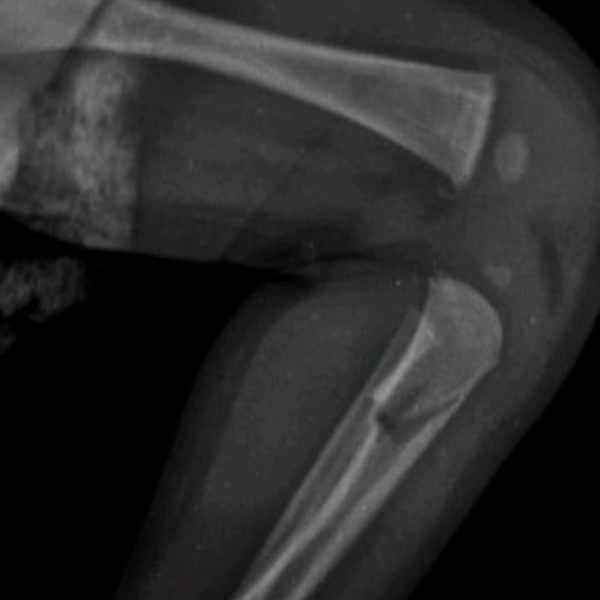

Exames de raio-X mostraram que além de hematomas e escoriações pelo corpo, o bebê também sofreu lesões ósseas em uma das tíbias, em um antebraço e também nas costelas. O laudo médico apontou ainda que os ferimentos expuseram o bebê a risco de vida.